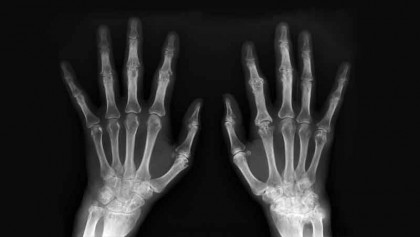

Arthritis is a debilitating disease that causes pain, stiffness and swelling from the inflamation of a joint or the area around joints. Arthritis is caused…

Arthritis treatment options

The treatment options covered in this article relate to osteoarthritis, although many of them may be effective rheumatoid arthritis treatments. Please…

When men get rheumatoid arthritis

What to do if joint pain turns out to be RA. For a few years, Andrew Ellis tried to tough out the pain, which started in his thumb. A boxer and football…

Rheumatoid and musculoskeletal diseases (RMDs)

RMDs are commonly classified into inflammatory and non-inflammatory types: Common non-inflammatory RMDs consist of degenerative spine diseases, osteoarthritis,…